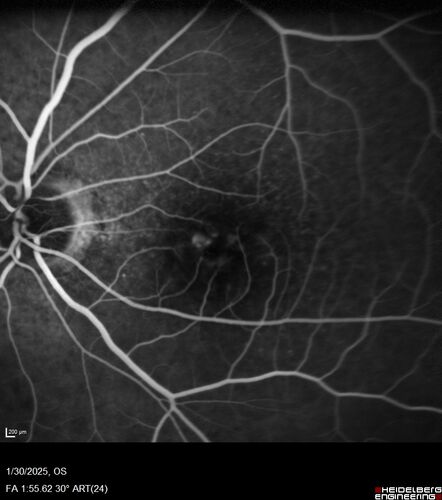

Conversion to Wet AMD after Izervay

83 year old man whose left eye had minimal GA and converted from dry to wet AMD after a single Izervay treatment

MNV_Izervay_99463_013025_12.jpg

Conversion to wet AMD on Izervay